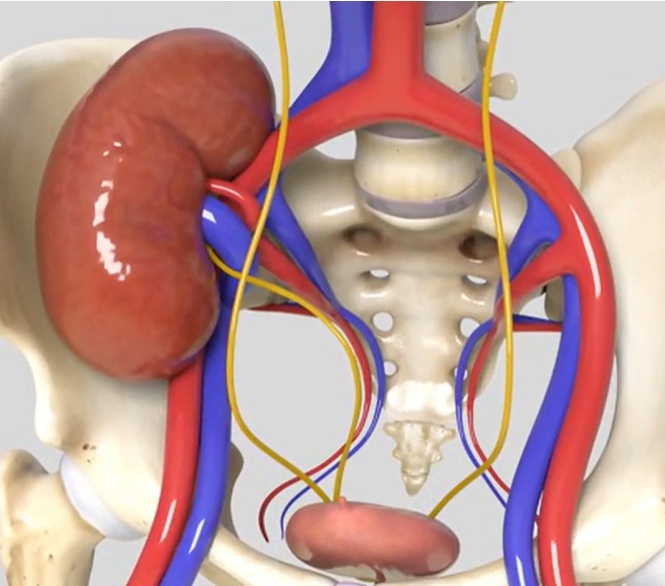

TRANSPLANTE RENAL

O Transplante Renal é o melhor tratamento para os pacientes com Doença Renal Crônica Terminal.

É um procedimento complexo que precisa de uma equipe multidisciplinar e é realizado somente em centros de referência.

Uma equipe cirúrgica experiente é fundamental para o sucesso da cirurgia

PIELOPLASTIA ROBÓTICA

É uma cirurgia minimante invasiva para o tratamento de estreitamentos (estenoses) do ureter, que é a estrutura por onde a urina passa do rim até a bexiga.

Seja congênita ou adquirida, a estenose de ureter pode levar a perda total da função renal se não corrigida a tempo

É uma cirurgia minimante invasiva para o tratamento de estreitamentos (estenoses) do ureter, que é a estrutura por onde a urina passa do rim até a bexiga.

Seja congênita ou adquirida, a estenose de ureter pode levar a perda total da função renal se não corrigida a tempo